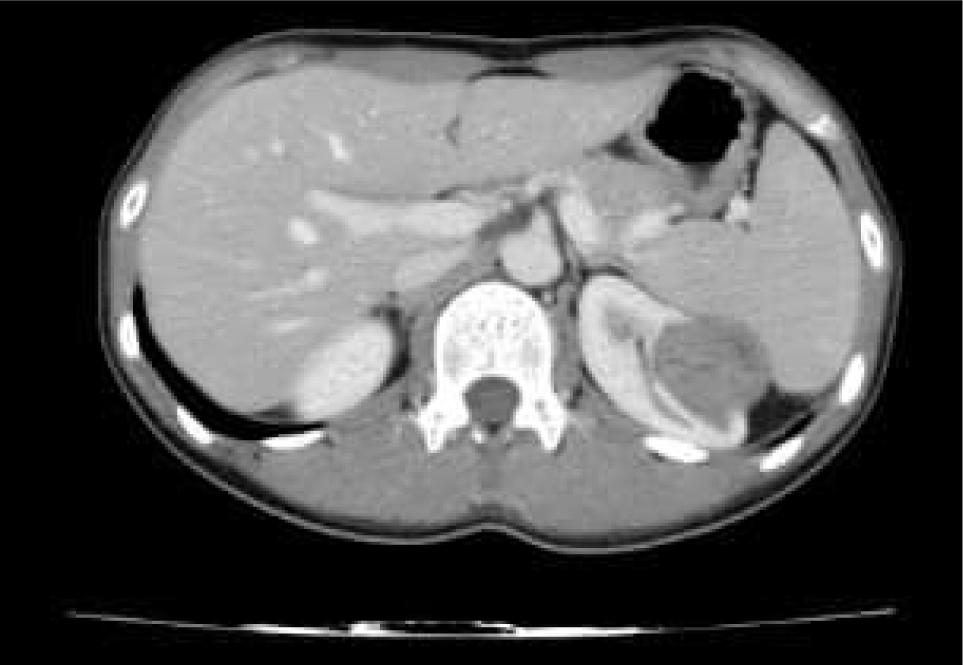

Nephroblastoma was diagnosed in first and second decade of life. Neoplasms were common on the left side (51.07%) as compared to the right side (48.92%). The tumour size ranged from 2 to 20 cm. The clear cell renal carcinoma was graded from 1 to 4 according to Fuhrman’s nuclear grading system. Nuclear Grade 2 was the most common (53.3%) features, followed by nuclear Grade 3 (23.33%) . Capsular invasion was seen in eight, vascular invasion in five, adrenal invasion in one and renal sinus invasion in 10 cases. Figures 14 show gross nephrectomy specimens. Figure 5 shows computed tomography (CT) images of RCC, and Figures 6 and 7 show the microscopic appearance of nephrectomy specimens.

Figure 5: CT image of Renal cell carcinoma.